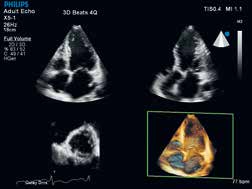

EPIQ 7C高端超声系统支持全面的具创新性的探头。只需一键按钮xMATRIX即可提供单探头的全模式应用:二维,M型,彩色多普勒,多普勒,iRotate智能旋转,实时二维切面,实时三维,实时三维缩放,及全容积实时三维。

nSIGHT使得强大的xMATRIX技术如虎添翼

使用实时任意多平面xPLANE同时创建多个全像素分辨率平面,让您在同一时间获得多倍临床信息。在全容积成像内以立方体素的分辨率来显示任何平面的图像。现在,一切都成为可能。

X5-1纯净波矩阵探头对二维、三维实时图像清晰度的体现。

纯净波矩阵探头还包括支持儿童三维成像的X7-2和支持3DTEE应用的X7-2t